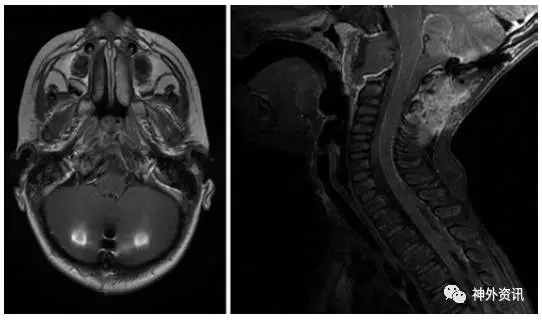

5岁男性患儿,诊断为斜坡脊索瘤(图1)。5年前行经口入路完全切除肿瘤(图2),术后进行质子束放疗。病理学检查报告为典型的脊索瘤,免疫组化提示角蛋白强阳性、上皮膜抗原强阳性、S-100免疫反应阴性和MIB-1标记指数为10%(图3)。术后因脑脊液漏反复出现脑膜炎,给予抗生素治疗后好转。接着继发交通性脑积水,通过脑脊液VP分流术降颅内压。术后5年发现肺部结节(图4),手术活检提示为低分化的脊索瘤,免疫组化结果和原发部位脊索瘤相似,即角蛋白强阳性和上皮膜抗原强阳性(图5),表明斜坡脊索瘤颅外转移。随后相继发生胸壁和颅骨转移。由于大部分脊索瘤mTOR通路激活,所以给患者使用伊马替尼联合雷帕霉素化疗后,肿瘤缩小,疼痛有所减轻。但是,9月后出现额部头皮肿物,并导致附近的VP分流管周围皮肤破溃。遂行头皮肿物切除和皮瓣转移术,以防止分流管暴露。免疫组化提示PD-L1高表达,即行PD-L1单抗治疗,胸痛明显缓解。6月后又出现新发的肺部转移灶,疼痛明显。免疫组化和基因检测为INI-1缺失,应用EZH2进行晚期解救治疗,疗效尚待评价。

图2. 术后MRI显示斜坡脊索瘤全切除。